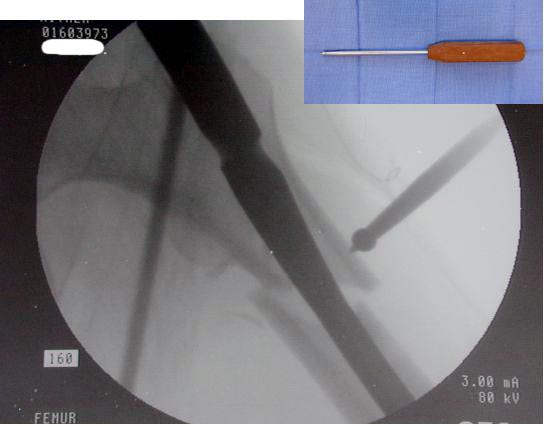

Большие преимущества у интрамедуллярных штифтов, метод хорош и можно произвести из минимального доступа, но во время операции необходимо контролирование варуса, затем приступить к блокированию.

Для молодых больных выбрал бы тактику fixed angled device 95 degree Blade Plate, техника непрямого метода репозиции, который описал в своей книге Jeff Mast, Planning and Reduction Technique in Fracture Surgery ( method of Inderect Reduction), репозиция и фиксация происходит за счет фиксации головки бедра к femoral shaft с помощью пластины, а что в середине должны репонироваться без больших усилии и без разрушения мягкотканого соединения c медиальной стороны.

слайды:

Long TFN

Short TFN

IMHS

DePuy Trochanteric Nail

Контролировать варус

Ap pelvis Rt sub-intra trochanteric Fracture, AP Rt hip, Postop Blade Fixation